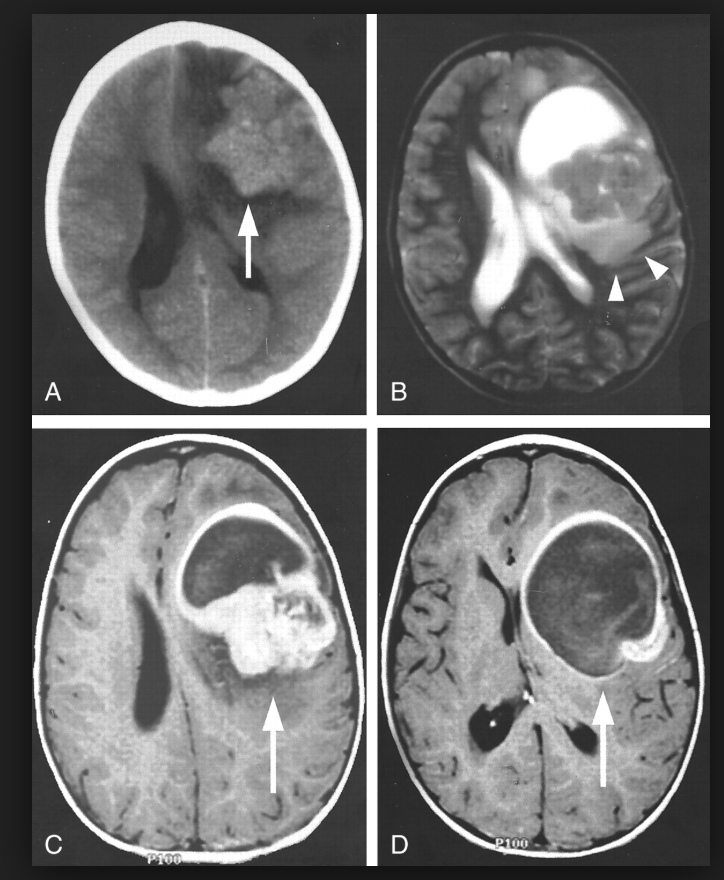

图4

图4 星形胶质细胞瘤